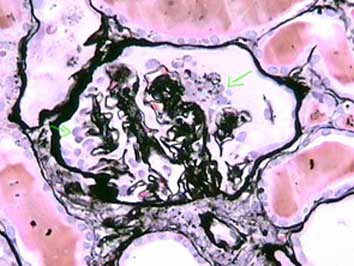

Figure 12. See the glomerular tuft collapse, without conserved capillary lumina, with an irregular aspect and wrinkling of the capillary walls and with marked hypertrophy and hyperplasia of podocytes. This case corresponds to a 37-years-old male patient with NS, HIV negative, and without other predisponent factors: primary collapsing FSGS (idiopathic). (Methenamine-silver, X400).